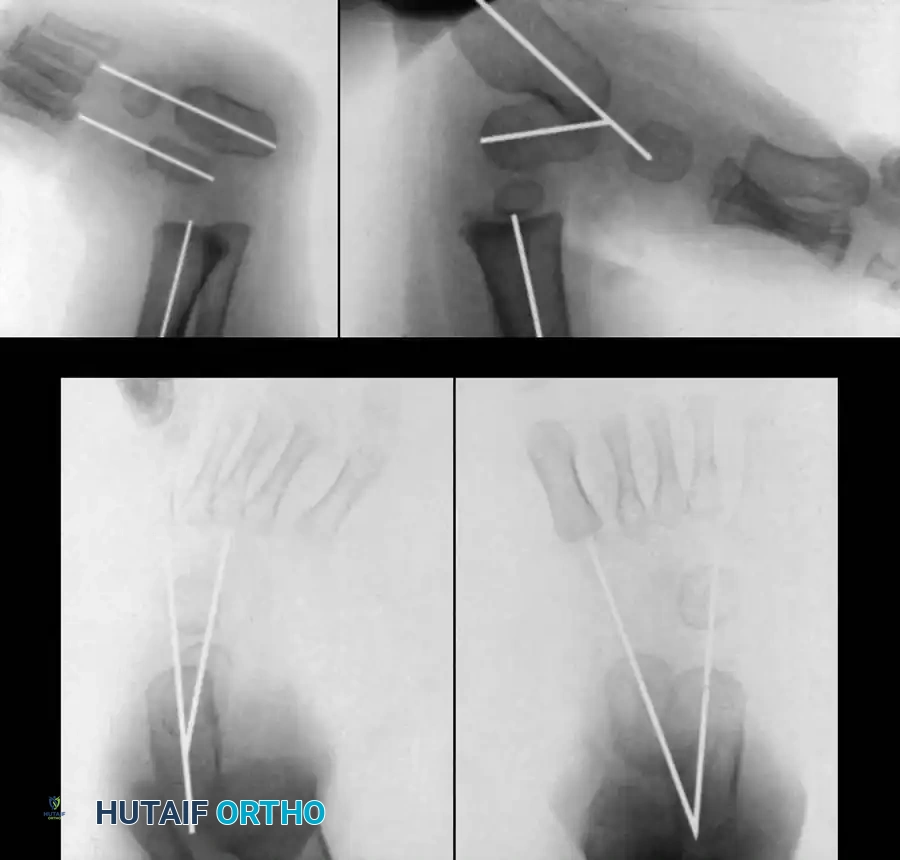

6. Reduction and Fixation:

* The navicular is reduced onto the talar head and pinned with a smooth Kirschner wire (K-wire).

* The calcaneus is rotated externally and translated laterally beneath the talus, correcting the varus and equinus. A second K-wire is driven from the heel across the talocalcaneal joint.

* Intraoperative radiographs are obtained to confirm the restoration of the talocalcaneal and talus-first metatarsal angles.

Image

Fig. 18: Intraoperative fluoroscopy confirming the reduction of the talonavicular joint and the placement of stabilizing K-wires.